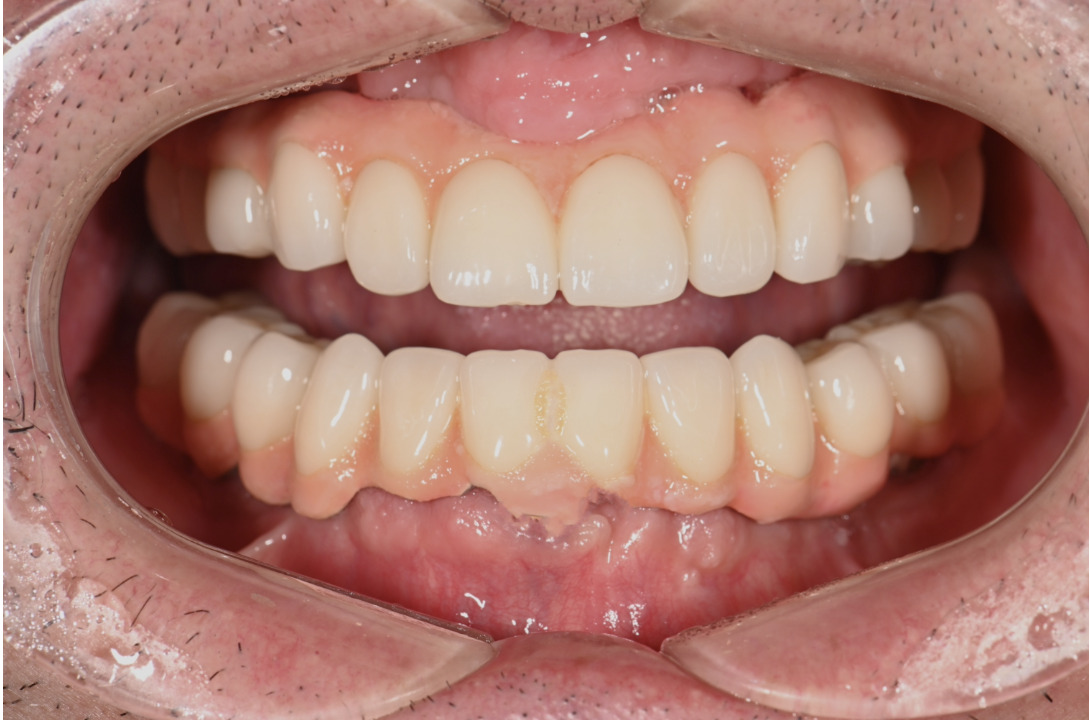

| 主訴 | 歯がグラグラして噛めない |

|---|---|

| 治療内容 | 上顎、下顎に対するインプラント治療 |

| 治療期間 | 1日 |

| 治療費 | 409万2千円 |

| 治療 リスク | 最終的な歯が入るまでは仮歯になります。 |